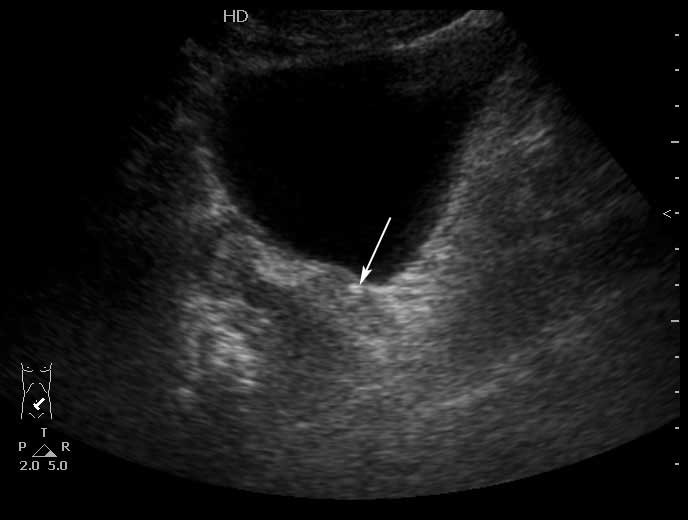

Конкремент в юкставезикальном отделе мочеточника. Пиелонефрит . Субкапсулярный выпот.

Да, МКБ,конкремент юкставезикального отдела мочетоника.

Выпот находится не под капсулой почки, а в периренальном пространстве в самой нижней точке человека прямоходящего.

Конкремент в юкставезикальном отделе мочеточника - стрелка.Брехт писал(а):Вокруг камни есть и отёчные стенки мочеточника?; или я допридумываю

Стенки мочеточника без существенных изменений.